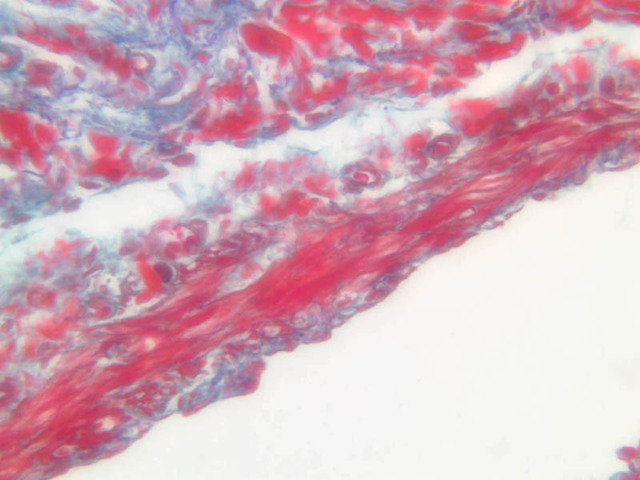

The blood is pumped from the heart into large, elastic (conduction) arteries. Examine a section of the aorta (A-26, H&E [2.5x, 10x, 20x, 40x-labeled] [2.5x, 10x-labeled, 20x, 40x]) which is a typical elastic artery. Although the tunica intima and tunica media are difficult to distinguish, note that together they are much thicker than the tunica adventitia. Using high power magnification, examine the tunica media and identify the cell types and fibers, recalling that elastic tissue appears light pink and refractive in H&E preparations. Compare this slide with a section of aorta stained to demonstrate elastic fibers (A-27, verhoeff [2.5x, 10x, 20x, 40x-labeled] [2.5x, 10x]).

Note how extensive the elastic tissue is in the tunica media. The elastic tissue is arranged in the form of numerous concentric elastic lamellae, which are cross connected by slender elastic fibers. Observe the distribution of elastic fibers in the tunica intima (A- 27 [2.5x, 10x, 20x, 40x]) and tunica adventitia (A-27 [10x, 20x, 40x]). The internal and external elastic membranes are not well demarcated in the aorta since so many elastic lamellae are present. The elasticity of the aorta allows it to expand and absorb much of the pressure during contraction of the left ventricle (i.e., systole). When the ventricle relaxes (diastole), the elastic aorta contracts, continuing the movement of blood into the medium and muscular arteries.